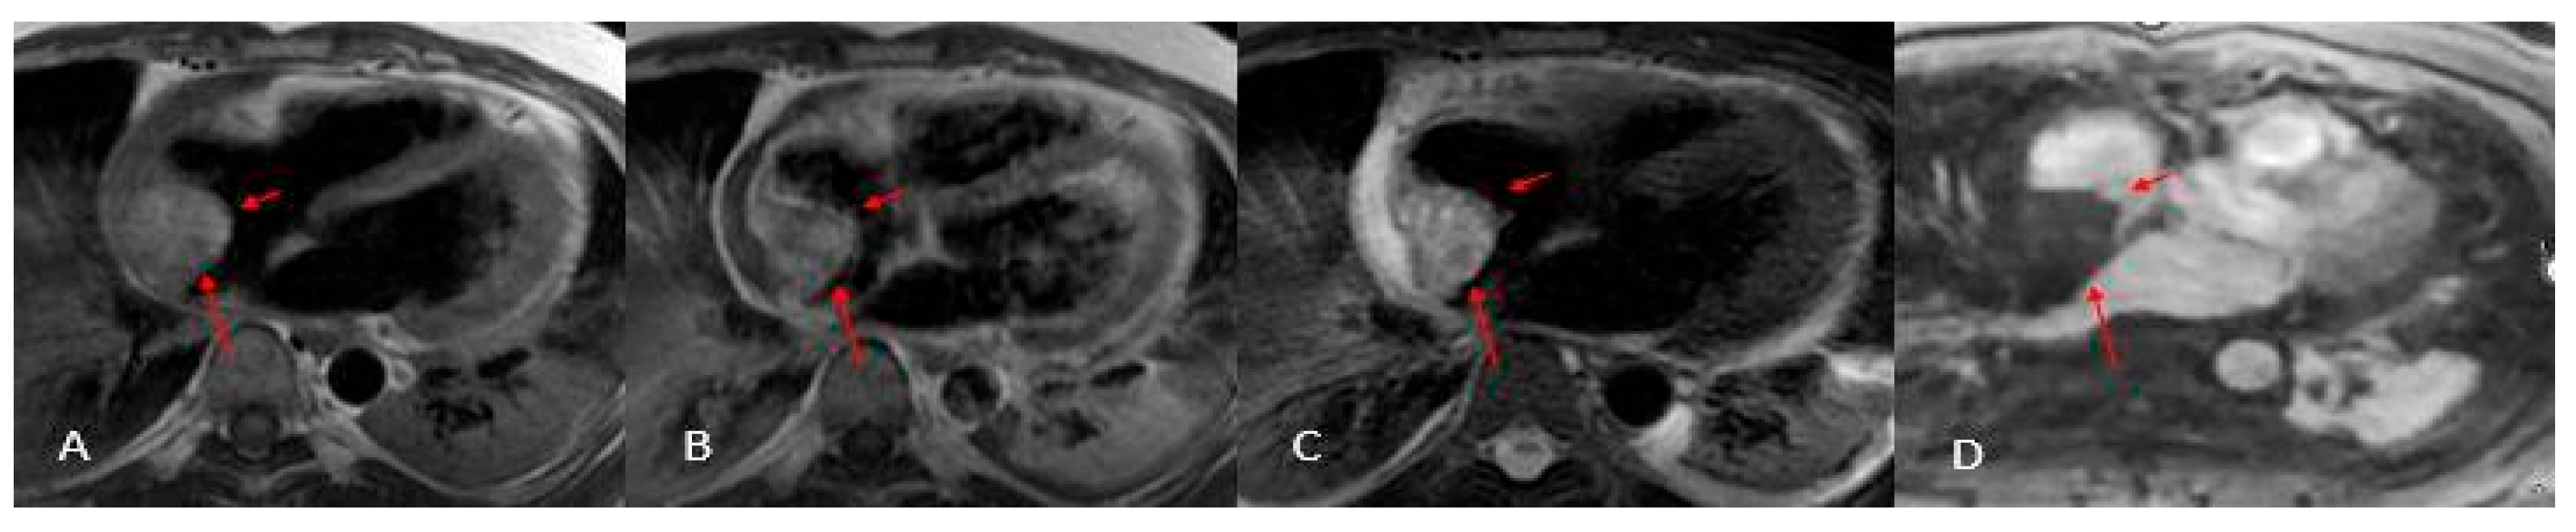

Thrombi reveal themselves as non-opacified (“vacuum”) areas after contrast injection (Figure 3)—critical to recognize for proper treatment—and are classically found in the left atrium of patients with atrial fibrillation. On CT they appear as hypodense, non-enhancing lesions [29]; on MRI their signal shifts with age: acute clots display intermediate intensity on both T1 and T2 (due to oxyhemoglobin), subacute thrombi become T1-dark and T2-bright as hemoglobin converts to methemoglobin and draws in water, and chronic, fibrosed clots lose water, appear dark on both T1 and T2, and generally lack contrast uptake (though longstanding fibrotic thrombi can show rim enhancement on delayed sequences), similar to normal fibrotic tissue [2,3,12,30].

Figure 3. Thrombus (white arrows). CINE (A), EGE (B), and LGE (C) sequences show a large thrombus (arrows) at the apex of the left ventricle. Note that it remains hypointense and does not take up contrast, which is typical of thrombi and helps in distinguishing them from other cardiac masses.